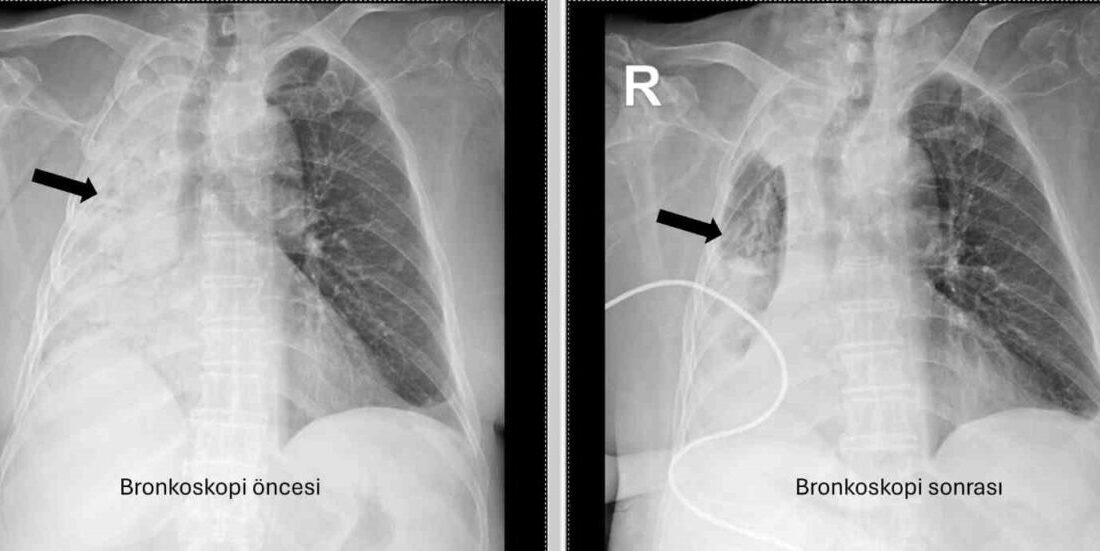

Denizli’de 78 yaşındaki felçli hastanın nefes borusuna kaçan mısır tanesi 5 ay sonra ortaya çıktı. Akciğerine enfeksiyonu şikayetlerinin tekrarlamasıyla ortaya çıkan olayda, yaşlı kadının sağ akciğerinin tamamen kapalı olduğu anlaşıldı.

Denizli’de yaşayan ve emekli öğretmen olan 78 yaşındaki felçli kadın son zamanlarda sık sık akciğer enfeksiyonu nedeniyle hastaneye gidiyordu. 1 ay önce gittiği hastanede bronkoskopi yapılmasına rağmen sorun saptanmadığı öğrenildi. Yaşlı kadının son gittiği hastanede sağ akciğerinin tamamen kapandığının tespit edilmesi üzerine Pamukkale Üniversitesi Hastanesine başvuruldu. PAÜ Hastaneleri Göğüs Hastalıkları Anabilim Dalı Öğr. Üyesi Prof. Dr. Göksel Altınışık Ergur, tarafından yapılan tetkiklerde sağ akciğere giden hava yolunun bütünüyle kapalı olduğu görüldü. hastaya acil bronkoskopi planlanıp hemen işlemin gerçekleştirildiğini söyleyen Prof. Dr. Altınışık Ergur, “Fleksibl (esnek, eğilip bükülebilir) bronkoskop ile hava yolları incelenirken çok yoğun ve koyu sekresyon olduğu, bunun iyice temizlenmesi sonucunda ancak hava yollarının incelenebileceği görüldü. Aspiratör (içerideki salgıları emmeye yarayan bir cihaz) sayesinde hava yollarına steril sıvı verilip emilerek bu temizlik yapıldı. Sonrasında sağ akciğere giden hava yolunda sarı bir nesne olduğu görüldü. Bu hâliyle yabancı cisim olduğu anlaşıldığı gibi bunun mısır tanesine benzerliği de açıktı. Yabancı cismi çıkarma işlemi genel anestezi altında, rijit bronkoskop ile yapılmak üzere planlanabilirdi; çünkü bu durumun tedavisi yabancı cismin oradan, ek sorun oluşturmaksızın çıkarmaktı. Ancak, genel anestezi altındaki bir işlem için hastanın genel durumu bozuk olduğundan, özellikle ek hastalıkları ve enfeksiyon varlığı ile işlem riski artacağından hastadaki cismin fark edildiği sırada çıkarılmasına şans vermek daha uygun görüldü. Hava yolu içindeki sıvıları emen aspiratörün gücünü kullanılarak cismin çıkarılması mümkündü. Bronkoskobun ucu, sarı cismin gövdesine dayanıp aspiratör ile emme sayesinde ikisi birbirine sımsıkı yapıştırıldı. Emme gücünün azaltılmamasına dikkat ederek yabancı cisim ve bronkoskop, aynı zamanda hava yollarından dışarıya başarı ile çıkarıldı. İşlem sonrasında hasta yakınına mısır tanesi açısından tıbbi öykü yeniden sorulduğunda, hastamızın bundan beş ay önce yediği pizzanın üzerinde mısır taneleri olduğu öğrenildi. O sırada ani bir yakınma ortaya çıkmadığı için böyle bir ihtimal akla gelmemişti. Düşkün hastalar taneli gıdalar yerken, bu durumun fark edilmeden de gelişebileceğini göstermesi açısından önemli olan bu tablo, hastaların bir dedektif titizliği ile değerlendirilmesi gerekliliğini bir kez daha ortaya koymaktadır” dedi.